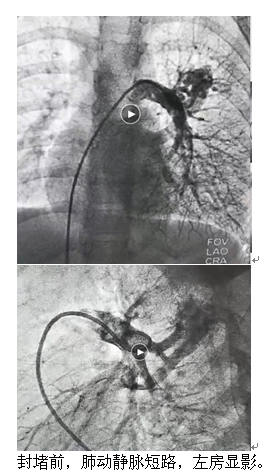

充分的完善術(shù)前準(zhǔn)備后,青島市婦女兒童醫(yī)院多學(xué)科聯(lián)合為夕夕完成了肺動靜脈瘺介入栓塞封堵術(shù),手術(shù)過程非常順利,心導(dǎo)管造影檢查進(jìn)一步明確診斷后,在DSA引導(dǎo)下用可控彈簧圈成功封堵了肺動靜脈瘺。